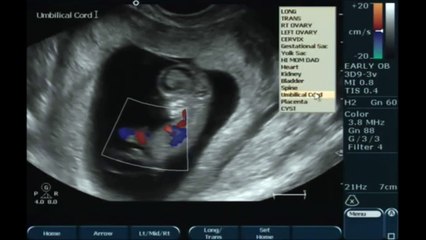

Geçtiğimiz günlerde, 24 haftalık prematüre olarak dünyaya gelen bir bebeğin hayata tutunma mücadelesi, aile ve sağlık camiasında büyük bir yankı uyandırdı.